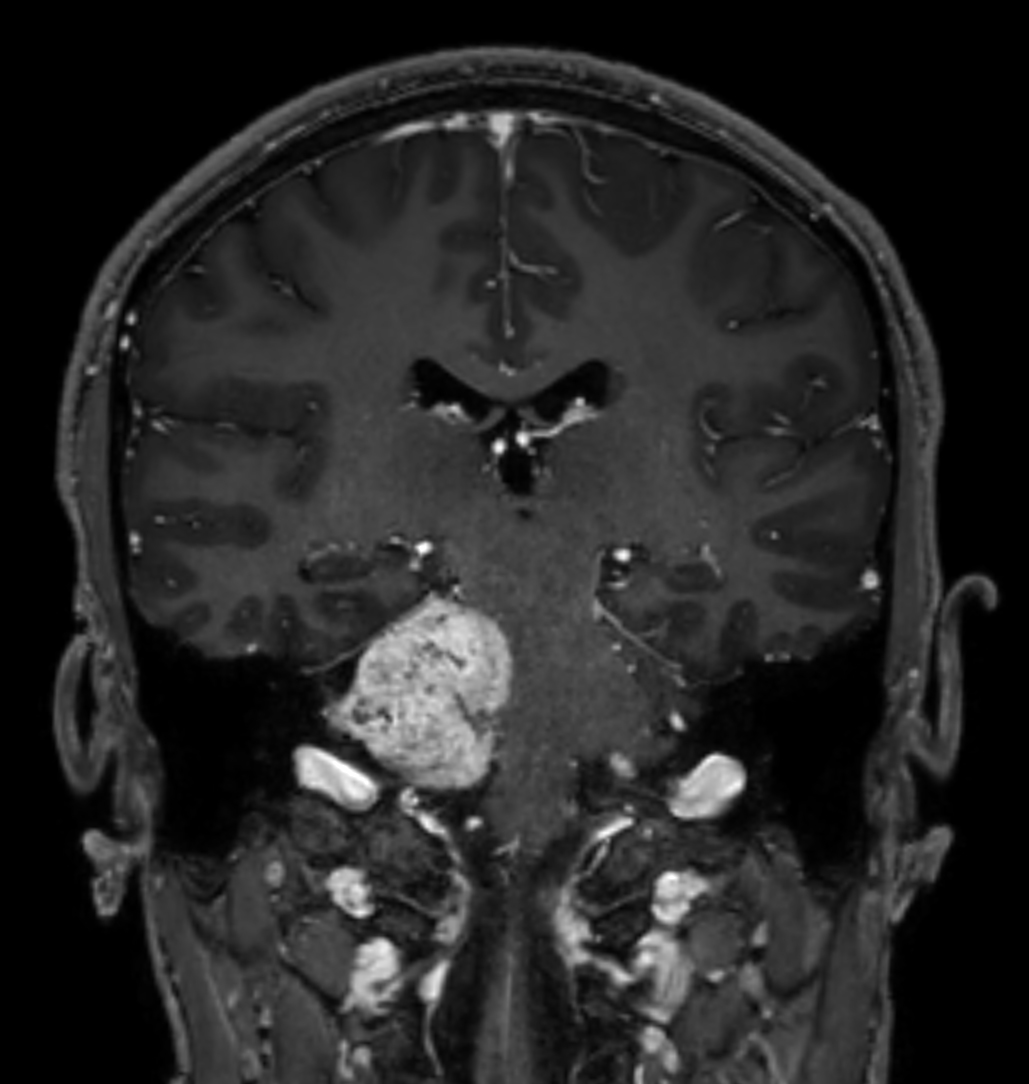

Patient with a brain (IAC) lesion. Compressed SENSE is used to shorten the scan time of the high resolution clinical scans, whilst MultiBand SENSE is used to reduce the scan time of the functional (DTI) scan.

Coronal 3D T1w TFE BrainVIEW with gado (reformat)